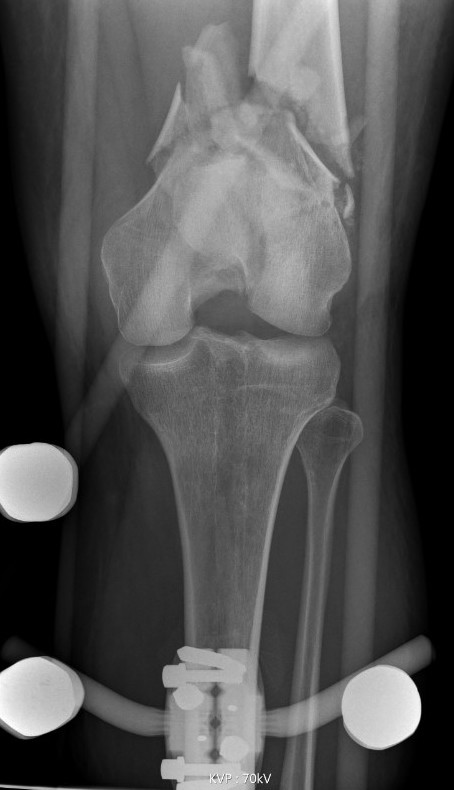

Type C: Complete articular

Xray / CT

Options